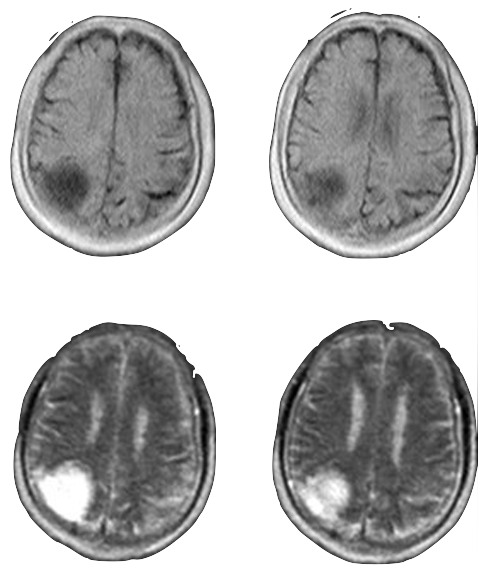

Traditional

3T MRI

AI-Driven

0.055T MRI

MRI source imagery: Liu et al., "A low-cost and shielding-free ultra-low-field brain MRI scanner" (Nat Commun, 2021)